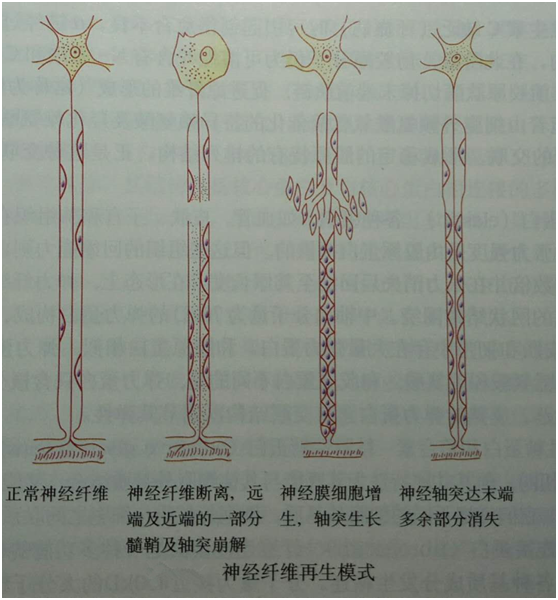

当神经纤维受损时,首先远端和近端的一部分髓鞘及轴突崩解,被吸收.

随着神经再生的进展,远端再生神经纤维逐渐成熟,直至出现一正常的有髄